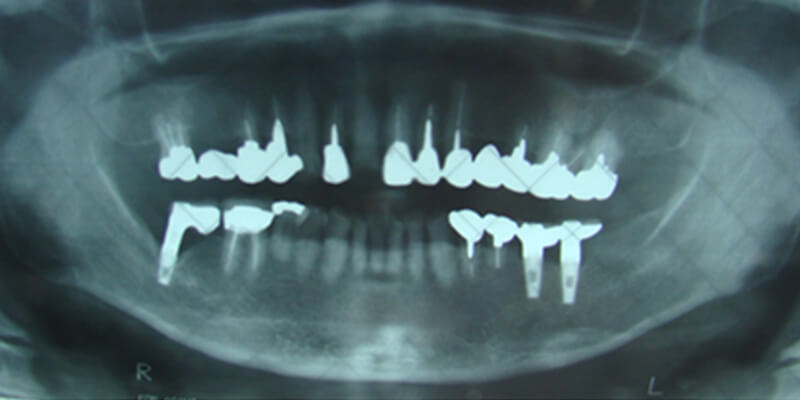

![]() | 奥歯が3本抜けてしまった状態です。従来はブリッジや入れ歯で治療していましたが、それでは残っている歯に負担がかかってり 、傷つけたりしてしまいます。 |

![]() | 残っている歯のために、インプラント治療を選びました。まず、歯が抜けてしまったところに、インプラントを植え込むためのスペースを作ります。 |

![]() | インプラントを植え込むためのスペースにもともとあった歯の形に合わせたインプラントを植え込みます。 |

![]() | インプラントを植え込んだら、歯肉で蓋をして約3ヶ月~6ヶ月待ちます。この期間を治癒期間と呼び、この間にインプラントが顎の骨と一体になります。 |

![]() | インプラントと顎の骨が一体になったら、インプラントに支台装置を取り付けて人工の歯をかぶせます。 |

![]() | インプラントによる補綴(歯の再建)処置が完成した状態です。歯があったときと同じ感覚が回復します。残ってい歯の状態も良くなります。 |

![]() | 完成です。 ※治療後について インプラントは人体との親和性に優れ、腐食しにくいチタン素材を使用していますが、治療後の清掃を怠りますと天然歯と同様に歯槽膿漏になり抜け落ちることもあります。定期的に健診を受けることがインプラントを長持ちさせる秘訣です。 |